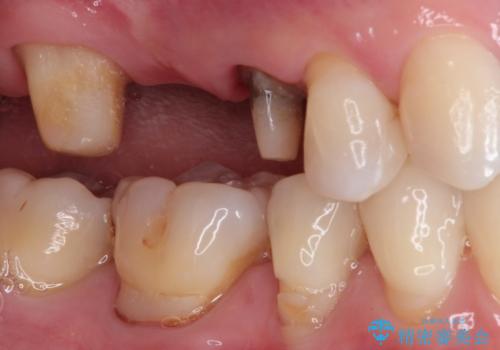

奥歯のオールセラミックブリッジ

- 矯正後に欠損補綴を主訴に来院されました。

オールセラミッククラウンのブリッジ修復にて治療を行っております。

抜歯してから歯周組織が安定するまで期間がかかります。

十分に期間を治癒を待つことで審美性や清掃性の高い被せものを製作できます。